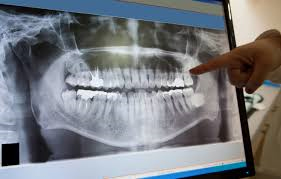

In Studio è possibile eseguire radiografie digitali a basso dosaggio di radiazioni, ortopantomografia (panoramica), radiografie endorali, bite-wing.